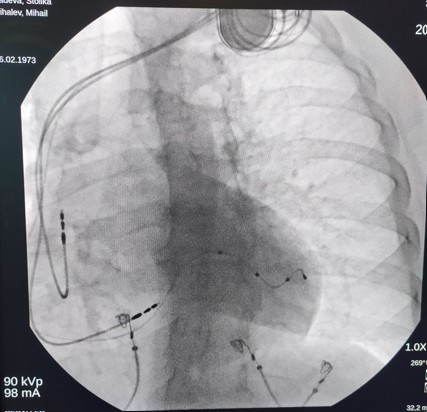

Методът представлява поставяне на електроди в проводната система на сърцето в областта на лявото бедро – т.н. физиологична стимулация, съчетано с поставяне и на електрод през коронарния синус в епикардната повърхност на лява камера. С помощта на устройство познато като пейсмейкър, се подават импулси по тези електроди, с което се постига синхронно съкращение на лявата камера на сърцето. Досега се поставяше електрод в дясната камера и в епикардната повърхност на лявата камера, за да се постигне синхронизация в съкращението на лявата камера, която страда повече при този тип на сърдечна недостатъчност.

Преди 3 месеца д-р Михаил Михалев, извършва първата такава процедура при 51-годишна жена, която страда от сърдечна недостатъчност, значително намалена помпена функция на сърдечния мускул и ляв бедрен блок на проводната система.

Кардиограмата на сравнително младата пациентка се подобрява веднага след процедурата. Днес тя има много по-стабилна помпена функция на сърцето, редуцирани са показателите на сърдечните обеми, поддържа много по-добра синхронност на лявата камера.

Преди две седмици д-р Михалев провежда същата процедура и при мъж на 70 години с подобни симптоми. Състоянието му в момента се проследява и вече показва значително подобрение на функцията на сърцето.